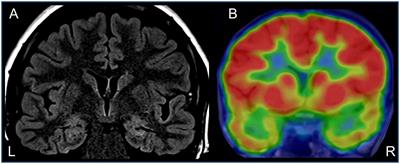

Activation of Functional Brain Networks in Children With Psychogenic Non-epileptic Seizures